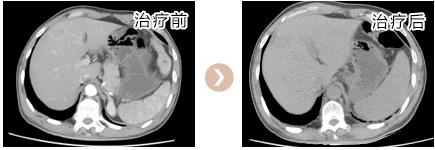

蔡##,男,53岁,2013.6.22因“1.直肠癌 2.右肝转移癌”入住我科,于2013.06.26行“CT引导下肝转移瘤射频消融术”,2013.06.27在全麻下行“腹腔镜下直肠癌切除术+横结肠造瘘术+左侧睾丸鞘膜翻转术”,术后病理PT4N2M1,术后恢复顺利,并予继续化疗等综合治疗,现定期门诊复查,未见复发转移,一般情况良好,生活质量高。

蔡##,男,53岁,2013.6.22因“1.直肠癌 2.右肝转移癌”入住我科,于2013.06.26行“CT引导下肝转移瘤射频消融术”,2013.06.27在全麻下行“腹腔镜下直肠癌切除术+横结肠造...